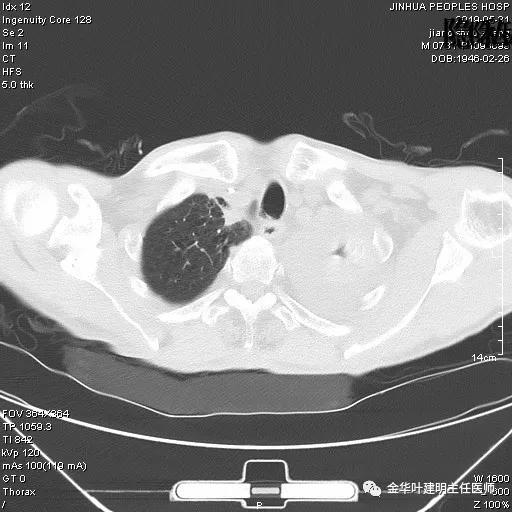

患者,男性,73岁,金华人。因“咳嗽咳痰伴胸闷2月,检查确诊左肺癌1周”入院。气管镜: 气管支气管内较多脓性分泌物,左肺上叶前段管腔新生物,局部活检、毛刷。气管镜病理:(左肺活检)鳞癌。阅胸部CT见左上叶开口处新生物,考虑需左上叶袖式切除及淋巴结清扫。具体CT表现如下: